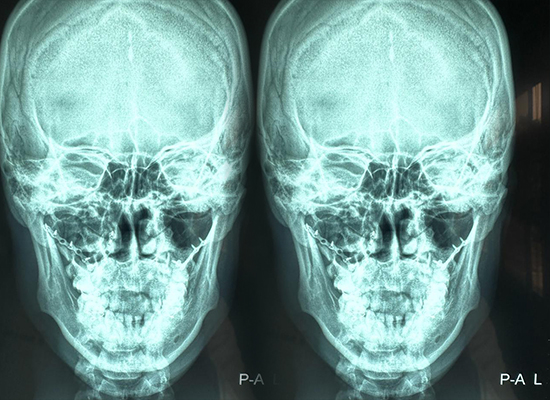

Las imágenes preoperatorias demostraron una inestabilidad significativa en la parte media de la cara, compatible con una fractura de Le Fort I que causaba problemas oclusales funcionales y alargamiento de la parte media de la cara. Estos patrones se asocian comúnmente con casos de reconstrucción con traumatismos faciales graves .